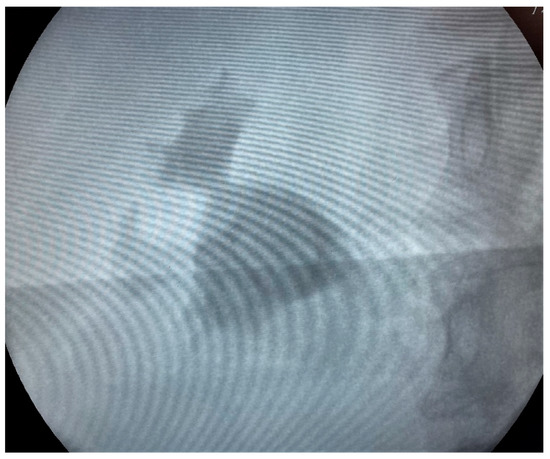

We proceeded with our standardized protocol of RIRS. Under general anesthesia, the patient was placed in the lithotomy position. At first, we performed a cystoscopy of the bladder. We found the right ureteral orifice and placed an ureteral catheter. Via the catheter, contrast agent was infused and, under fluoroscopy, the renal collecting system and the calculi was detected (Figure 1). The insertion of the guidewire followed, an ureteral access sheath was placed and through it we reached the kidney with a flexible ureteroscope of 8.6 French. The stones were found in the upper calyx and in the pelvis (Figure 2) so we began lithotripsy using holmium laser, checking throughout the whole procedure with fluoroscopy. In the meantime, the contrast agent was almost eliminated from the pelvicalyceal system and the stones were efficiently exported. Although we could not see any other calculi in the system, in the fluoroscopy there seemed to be one more (Figure 3). Therefore, we continued our endoscopy in order to find it. We came up to a small aperture in the spot that was indicated to us by the fluoroscopy, so we diagnosed an infundibulum stenosis and thought that the calculi would be within the calyx. The ureteroscope could not be inserted due to the stenosis, so we used the laser to widen the aperture. When the bore was opened and the access to the calyx was provided (Figure 4) we still could not found any calculi. In the fluoroscopy the sign has disappeared (Figure 5) so we understood that the contrast agent was entrapped in the calyx mimicking a stone in the fluoroscopy. The patient was stone free. We placed a double-J stent according to our protocol and the operation has ended. The patient the next day was free to leave the hospital without any complications, according to Clavien–Dildo system.

In our case, there were no signs of a dilating calyx in the CT and the pain occurred concomitantly with the stone formation, with no previous symptoms suggesting evaluation of the upper tract. During fluoroscopy, the sign that drew our attention was a radiopaque lesion that seemed similar to a stone fragment, while the contrast agent has left the pelvicalyceal system—or so we thought at that time. Throughout the inspection, no stone was found and, using fluoroscopy, we came up with the small aperture that turned out to be an infundibular stenosis as described before. Any CT or fluoroscopic image showing lithiasis that cannot be found during endoscopy should suspect the urologist to an entrapped calyx.

Figure 3. Fluoroscopy Image at the end of the lithotripsy.